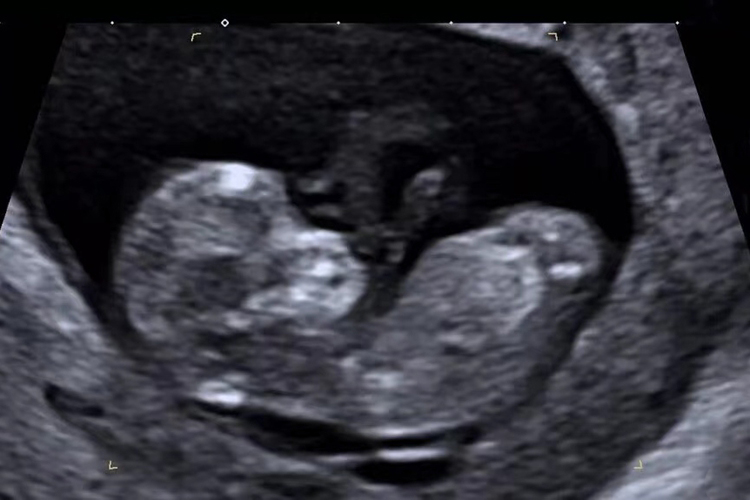

胎儿12周可通过超声检查来观察胎儿的发育情况,一般可分辨出胎儿的眼、耳、鼻、口等,同时,外生殖器也已发育,可辨别出性别。

胎儿12周的发育情况可通过超声明确,一般提示顶臀长为6-7cm,外生殖器已发育,部分可辨出性别,多数胎儿骨内出现骨化中心,指(趾)开始分化,皮肤和指甲出现,胎儿四肢可活动。同时还能分辨出胎儿的眼、耳、鼻、口等。因胎儿12周已经形成心脏,此时还可见到心脏搏动。